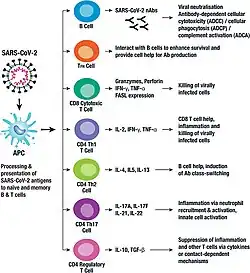

Inmunidad

La respuesta inmunitaria natural de los seres humanos al virus SARS-CoV-2 se produce como una combinación de la inmunidad mediada por células y la producción de anticuerpos, igual que con casi todas las otras infecciones.[143] Las células B interactúan con las células T y comienzan a dividirse antes de la selección en la célula plasmática, en parte sobre la base de su afinidad por el antígeno. La presencia de anticuerpos neutralizantes en la sangre se considera una prueba de inmunidad contra la infección, pero el nivel de anticuerpos neutralizantes disminuye con el tiempo, llegando a desaparecer tras tres meses en el 1% de los pacientes y tras seis meses en el 12%.[144] Sin embargo, la ausencia de anticuerpos en la sangre no significa que el sistema inmunitario no pueda producir nuevos anticuerpos rápidamente en caso de reexposición al SARS-CoV-2. Las células B de memoria específicas para las proteínas de la nucleocápside y el pico del SARS-CoV-2 duran al menos 6 meses después de la aparición de los síntomas.

La inmunidad innata frente al SARS-CoV-2 se utilizan principalmente por macrófagos y Células NK,en la inmunidad celular se utiliza por células dendriticas,linfocitos T CD4+ y linfocito T CD8+, y también en la inmunidad humoral la primera línea de defensa se utiliza la IgM y después la IgG, las citocinas implicadas en la inmunidad es el balance entre proinflamatorio y antiinflamatorio (IL-1β, IL-1RA, IL-2RA, IL-6, IL-7, IL-8, IL-9, IL-10, FGF básico, G-CSF, GM-CSF, HGF, Interferón gamma, IP-10,MCP-1, MIP-1a, MIP-1b,PDGF, TNF-α, VEGF y TGF-beta), la duración es alrededor de 2 semanas.[156][157][158][159] La presencia de algunas variantes en loci de las secuencias del gen del interferón reduce la inmunidad natural y estimula la susceptibilidad a enfermedades virales graves, incluida la COVID-19.[160][161]